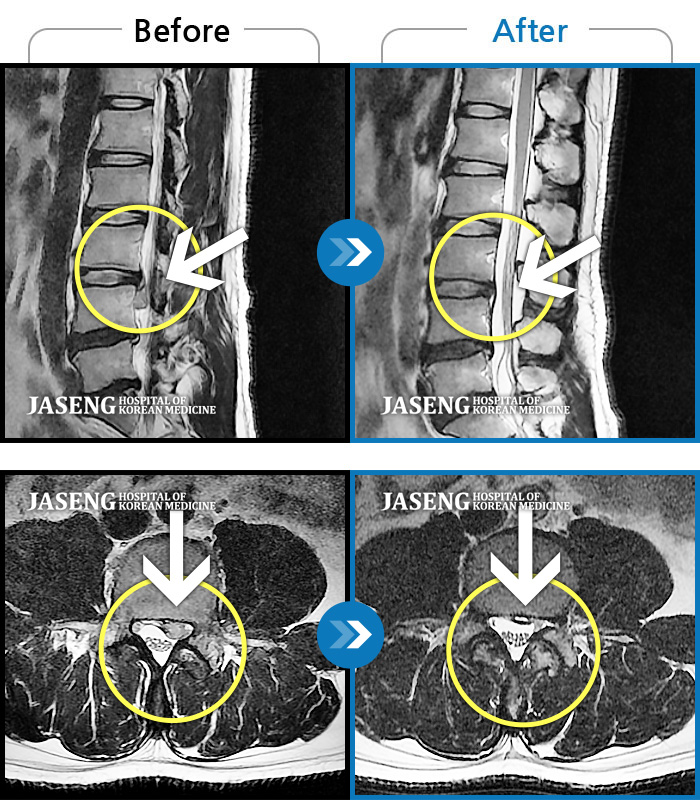

Before

After

환자에게 사전 동의를 받아 동일 조건에서 촬영되었습니다.

개인에 따라 치료 후 부작용이 발생할 수 있으니 의료진과 상담 후 치료를 진행하시기 바랍니다.

허리디스크로 인한 요통

허리 디스크 수술 후 재발된 디스크 환자